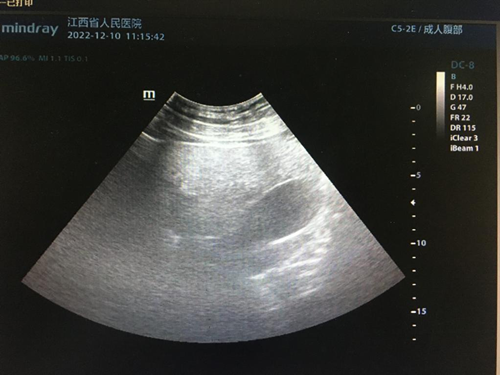

(1)轻、中度脂肪肝:肝大小正常,实质回声均匀、细密、轻度增强,轻度脂肪肝的肝内管道结构清晰,中度脂肪肝的肝内管道结构稍模糊,但仍可辨认清楚,后方回声轻度衰减,深面膈肌可显示。

(2)重度脂肪肝:肝脏体积增大,形态饱满,肝回声均匀、细密、明显增强,肝内管道结构模糊不清,后方回声明显衰减,深面的膈肌显示不清。